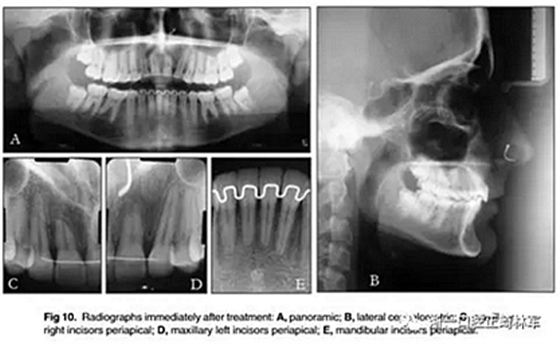

最終的X線評估(圖10)表現(xiàn)出良好的根并行性。上頜中切牙有嚴(yán)重的牙根吸收。然而,臨床上這些牙齒的牙周穩(wěn)定性良好。頭影測量分析顯示上頜骨和下頜骨門牙的傾斜度和位置良好。在治療期間觀察到幾乎沒有骨骼改變。

6年后治療結(jié)果保持穩(wěn)定(圖11,圖12 ; 圖13)??梢杂^察到穩(wěn)定的間隙關(guān)閉,正常的覆蓋和覆合,上下牙中線一致,微笑美觀。建議完美替代了拔除的側(cè)切牙。正畸治療后進(jìn)行牙齒美白。